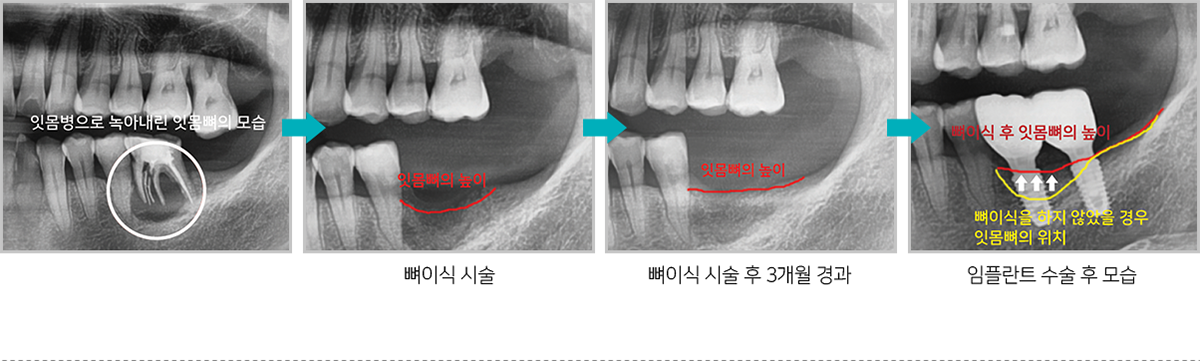

치조골은 치아를 발치 한 후 지속적으로 녹아

없어지는데 치조골을 보존하기 위해

발치 후

미리 뼈이식 하면 추후 임플란트 식립시 충분한

치조골을 확보할 수 있어

임플란트 수술을 하는데

매우 유리합니다.

뼈이식 시술 후 잇몸뼈의 위치 변화